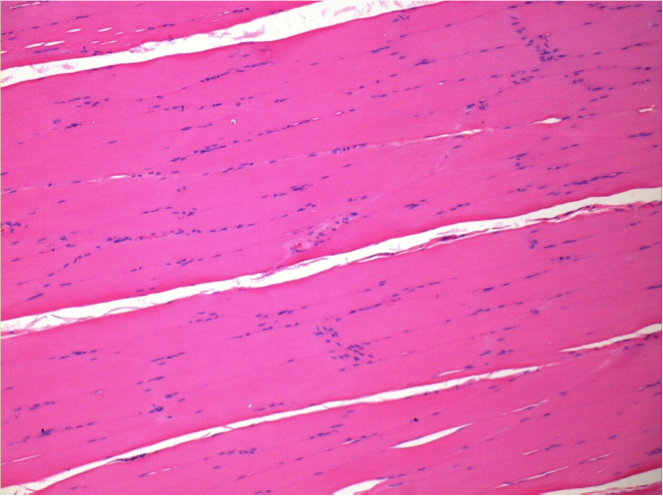

L:Pretibial-No treatment

10 days after Endopeel Injection 0.1ml in the right pretibial muscle.